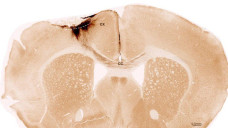

Thí nghiệm của các nhà khoa học Mỹ và Thụy Sĩ đã vạch ra con đường mới để phát triển các phương pháp giúp người bị đột quỵ phục hồi tổn thương não.